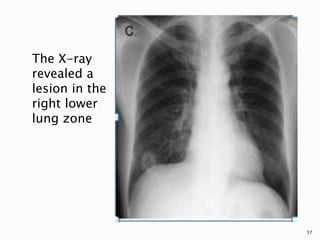

The X-ray

revealed a

lesion in the

right lower

lung zone